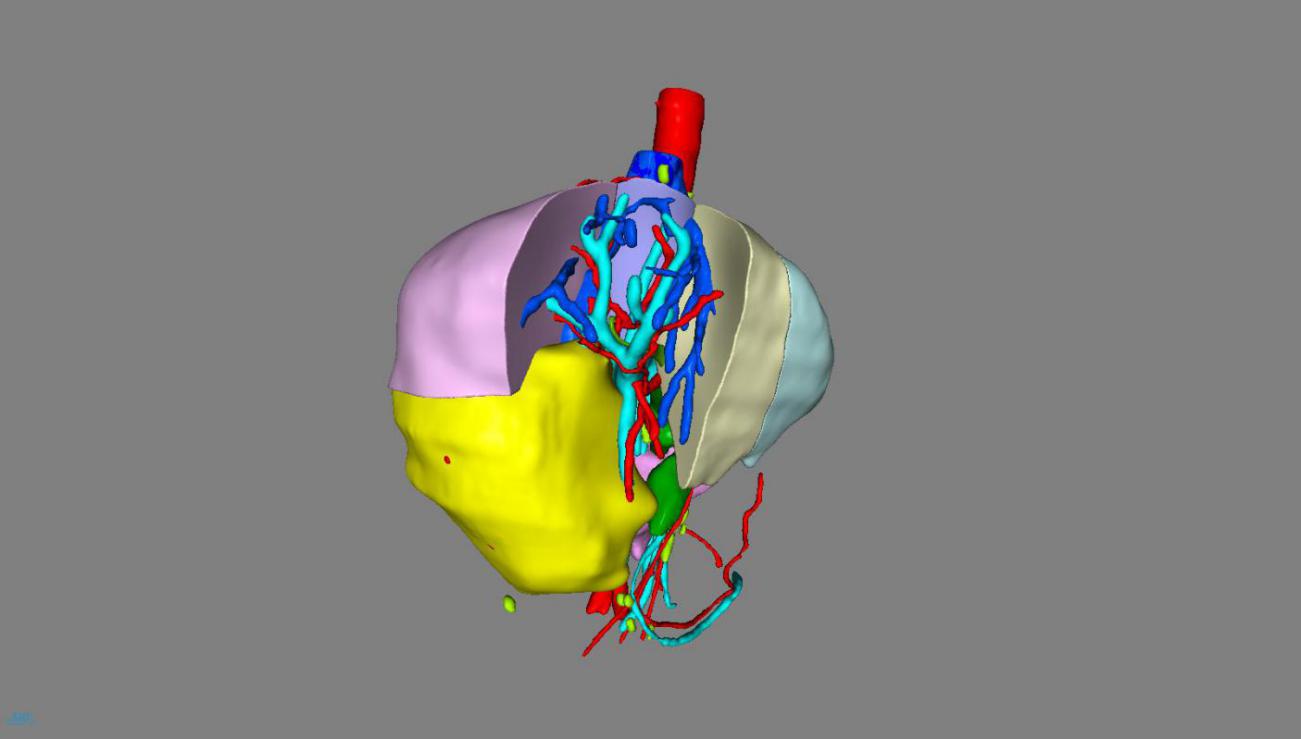

一、术前利用计算机3D模拟可视化技术测算肿瘤的体积和形态、癌栓的位置、血管的走行以及切除肿瘤后剩余肝脏的体积,制定了首选手术方案及备选手术方案;

经过周密的术前准备,2018年10月17日,肝胆外科李晓武教授团队给患者实施了精准右半肝切除术。术中探查结果与术前规划基本一致,整个手术历时2.5小时,术中釆用凝血器切肝,半肝血流阻断,切肝时间18分钟,切肝过程“0”出血,“0”输血,整个手术过程出血100ml。标本大小13*10cm,完美展现了精准肝切除、无血肝切除的理念。术后,患者生命体征平稳,清醒后送回普通病房。